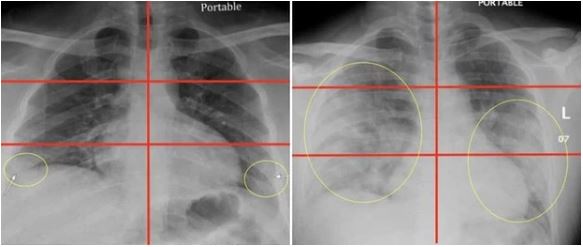

Qua hình ảnh có thể thấy, phim chụp X quang phổi của bệnh nhân Covid-19 bị "trắng đục" hơn và tổn thương nặng hơn so với phổi của người hút thuốc lá lâu năm.

Bác sĩ Brittany Bankhead-Kendall, phó giáo sư phẫu thuật tại Đại học Công nghệ Texas, Mỹ viết rằng, phim X quang phổi giống như một bộ phim đen trắng. Xương, cơ quan và cơ quanh phổi của những người khỏe mạnh có màu trắng, và toàn bộ phần lớn là màu đen.

Các chất khác nhau có thể chiếm không gian phổi, bao gồm chất lỏng, cục u, sẹo mô hoặc các hiện vật khác, sẽ xuất hiện giống như khói trắng tùy theo mật độ của chúng, còn được gọi là "độ mờ kính".

So sánh hình ảnh chụp X quang phổi của người hút thuốc lá và bệnh nhân mới bị nhiễm Covid-19, người ta thấy rằng phổi của người hút thuốc lá có đầy sẹo và những sợi chỉ trắng xung huyết, còn của bệnh nhân nhiễm Covid-19 cũng có hình sẹo giống như vậy nhưng số lượng lớn hơn, lan ra ở khắp phổi.

Tình trạng phổi của bệnh nhân Covid-19 thậm chí còn tồi tệ hơn một số người hút thuốc lâu ngày.